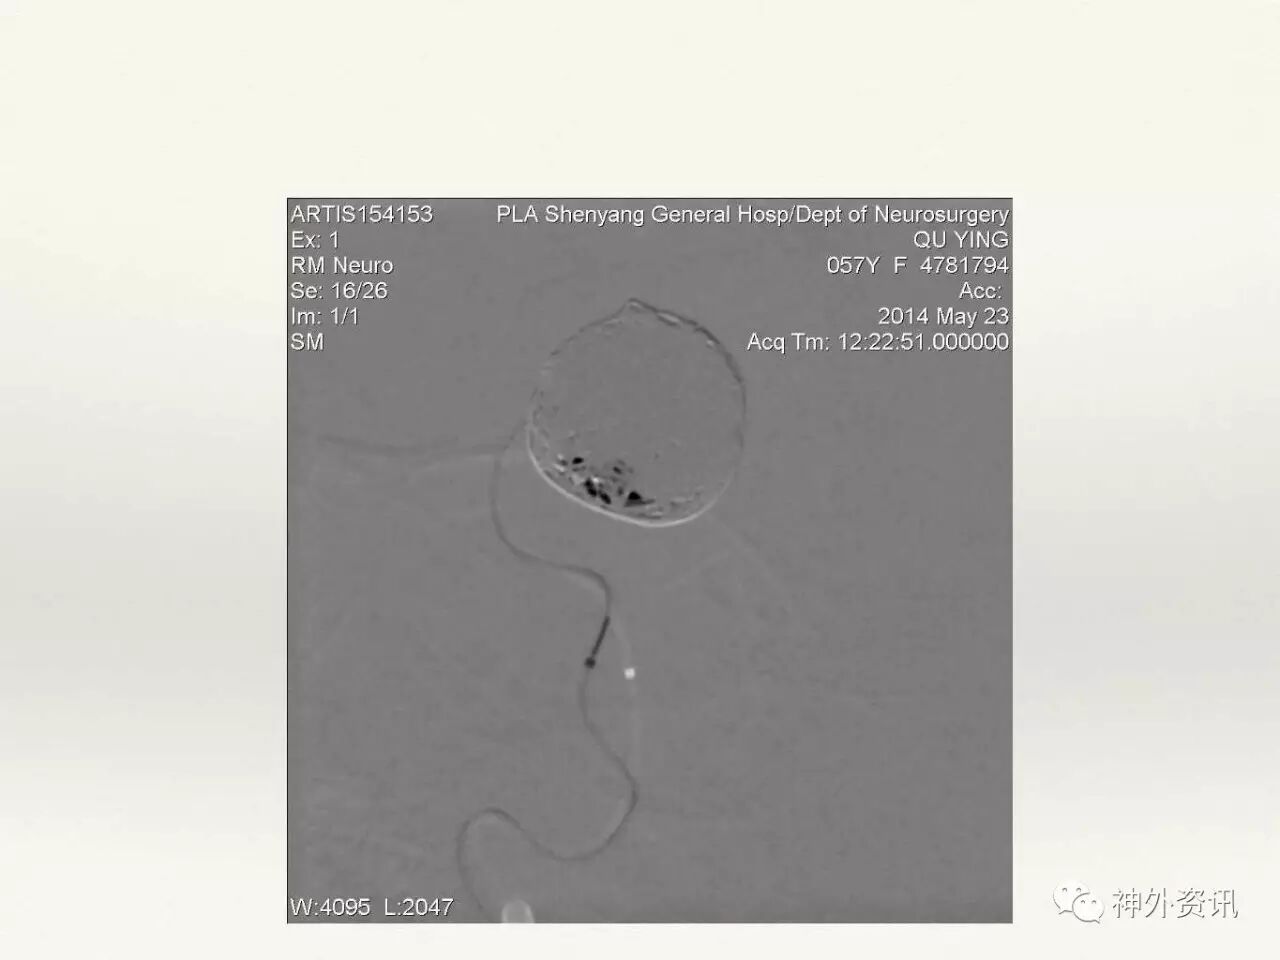

在东北地区率先开展了颈内动脉、大脑中动脉及基底动脉闭塞血管内再通、颅内动脉栓塞急性期取栓、血流导向装置治疗大型宽颈动脉瘤等,对颅内动脉瘤、动静脉畸形、颈动脉及颅内动脉狭窄、颈内动脉海绵窦瘘、硬脑膜动静脉瘘等外科治疗具有较深的造诣。完成脑血管造影8600余例,各类脑血管病介入手术共4500余例,动脉瘤、动静脉畸形、脑肿瘤、脑出血及脑外伤等外科手术1500余例。